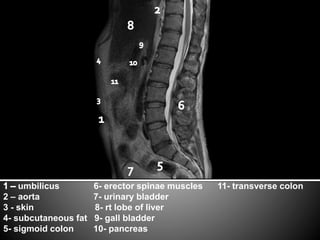

This document lists anatomical structures in the human abdomen including the umbilicus, aorta, skin, subcutaneous fat, sigmoid colon, erector spinae muscles, transverse colon, urinary bladder, right lobe of liver, gall bladder, and pancreas.